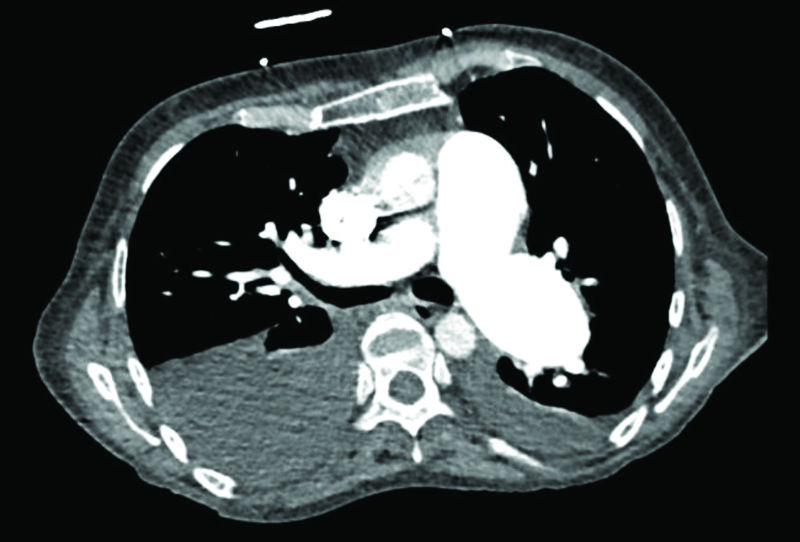

Laboratory results showed markedly elevated D-dimer levels at 10.5 mg/L (reference range: 0.19–0.50 mg/L). A chest x-ray indicated cardiomegaly with changes suggestive of pulmonary edema. Computed tomography with angiography revealed cardiomegaly with bilateral pleural effusions and diffuse dilatation of the pulmonary arteries, indicating significant pulmonary hypertension or overcirculation (Figure 1 and Figure 2). A transthoracic echocardiogram (TTE) identified a large secundum ASD with elevated right ventricular pressure measuring 70–74 mmHg. Flattening of the interventricular septum was also observed, further supporting the diagnosis of elevated right ventricular pressure. The TTE also revealed severe muscular and dynamic right ventricular outflow obstruction and pulmonary valvar stenosis. The patient was started on a diltiazem drip, and the cardiology service was consulted for transesophageal echocardiogram (TEE) guided cardioversion. The TEE confirmed the presence of a large ASD, and the bubble study indicated primarily left-to-right shunting, with a possible ventricular septal defect (VSD). Both atria appeared enlarged, but no intracardiac thrombus was detected. The patient underwent electrical cardioversion and successfully returned to sinus rhythm.

Figure 1

Figure 1. Transverse view of the thorax demonstrating markedly dilated pulmonary arteries and bilateral pleural effusion, with greater effusion observed on the right hemithorax.